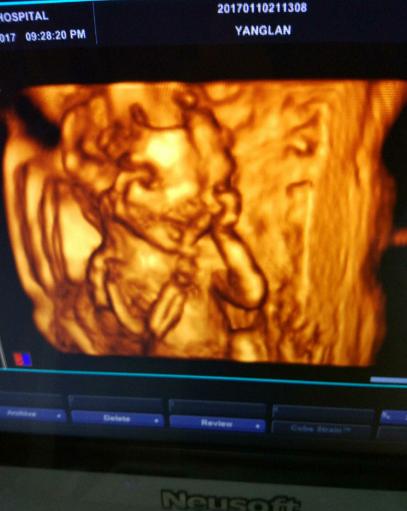

四维彩超宝宝开心 (四维彩超顺利通过宝宝很配合)

朋友怀孕几个月了,每隔一段时间就去检查。迫切地想知道肚子里是个“小鸡妞”,还是“小鸡仔”。前两天又去医院做了唐氏筛查,医院刚好新进了四维机,说是能看到辨别宝宝的性别,朋友兴奋的不得了,于是赶快做了一个检查。第一次看到宝宝动,好激动,医生很仔细的帮看,老公也在看,医生看大腿小鸡鸡好明显,我老公说小鸡鸡耶,医生说看到没有凸起来的那个就是小鸡鸡,朋友说:“听到自己肚子里是个小鸡仔的时候,眼泪不自觉地流了下来。”